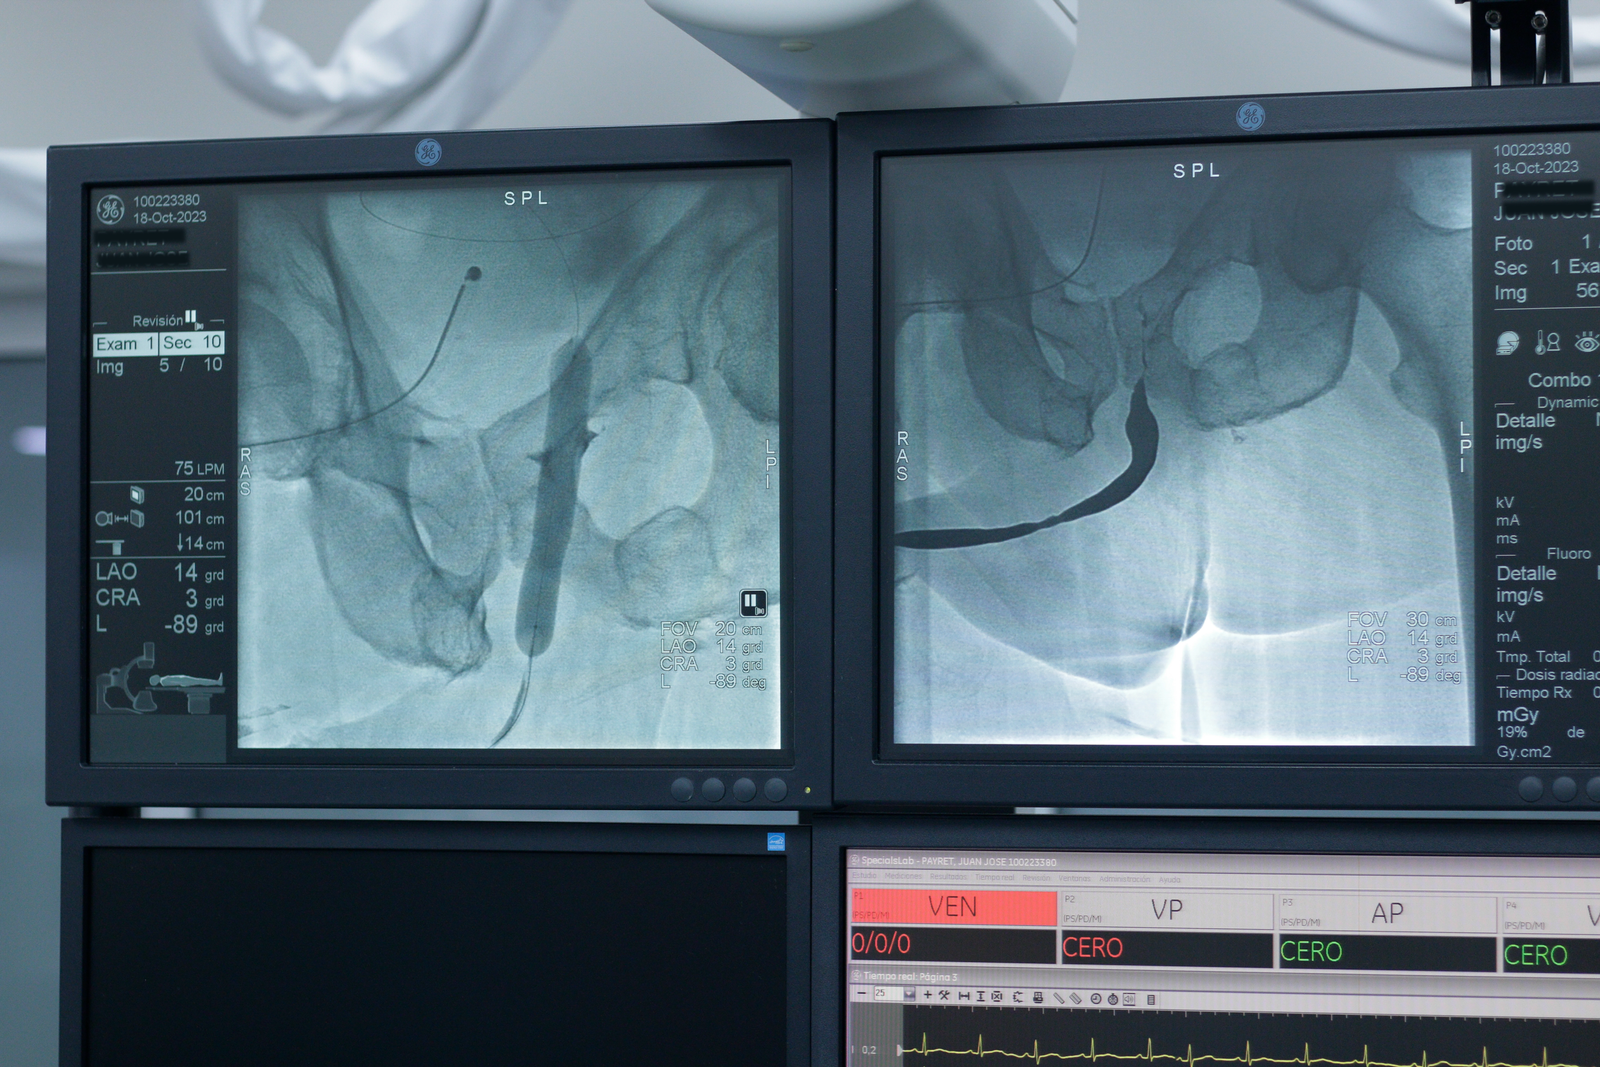

Uretroplastía procedimiento combinado mini Uretrotomía interna cutting balloon balón con paclitaxel